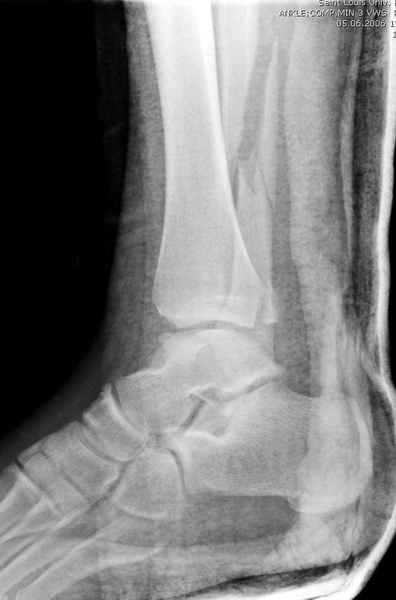

>На сделанных у нас снимках видно, что не все благополучно...

Неравномерность суставной щели может быть связана с разрывом глубокой порции дельтовидной связки и ротацией м/берцовой кости за счет поврежденных структур синдесмоза(репозиция ее на уровне перелома как-будто удовлетворительная).

По моему мнению,ассиметрия суставной щели обусловлена импрессией медиальной части суставной поверхности б/б кости. Да, позиционный винт здесь не лишен, но через 4 недели целесообразность его проведения сомнительна, брейс, ограничение осевой нагрузки достаточно.Есть еще деонтологические аспекты повторной операции, не все так плохо выполнено предыдущим доктором!

Импрессия медиальной части суставной поверхности бывает при супинационном механизме перелома лодыжек (тип А по классификации АО). Здесь механизм пронациия+наружная ротация (тип С, синдесмоз и межкостная мебрана повреждены),

перелом медиальной лодыжки отрывной, при этом в 20-30% бывает повреждение дельтовидной связки.

Мое мнение, что никакой ротации малоберцовой кости здесь нет и синдесмоз тоже впорядке. Все дело в некачественно репозиции медиального мыщелка. Скорее всего его или немного ротировали при операции или сместили латерально. Более склонен ко второму варианту.

Конечно, компьютерный томограф более информативный метод, но с помощью недорогого обычного стандартного в нейтральном положении стопы: прямого, бокового и косой (ankle mortise) ренгенологического метода можно получить полную информацию о повреждении голеностопного сустава, а сравнительный снимок с другой стороны подтвердить наличие повреждения.

При реконструкции голеностопа, о важности восстановления длины малоберцовой для профилактики пост травматического артроза разбирали в предыдущих дискуссиях. Нарушенную биомеханику голеностопа без восстановления длины малоберцовой, не восстановить только швом медиальной связки.

Расширенная медиальная щель более чем на 4 мм и укорочение малоберцовой более чем 2 мм, а перелом заднего края большеберцовой смещения более 2мм с вовлечением 30% поверхности сустава, считается отходом от нормы голеностопного сустава, и подлежит к оперативному вмещательству.